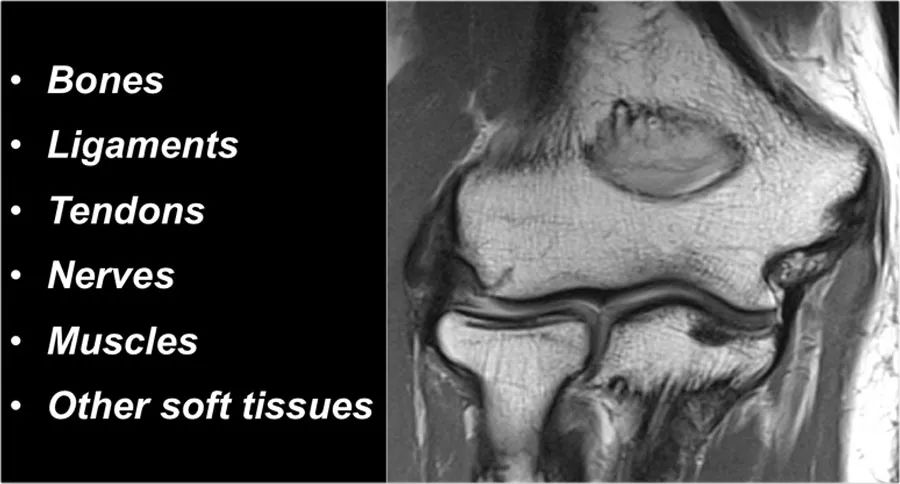

当你研究肘部的解剖结构时,最好使用由内而外的方法。首先研究骨骼,然后继续韧带和肌腱,然后是周围的结构。

影像检查与解剖基础